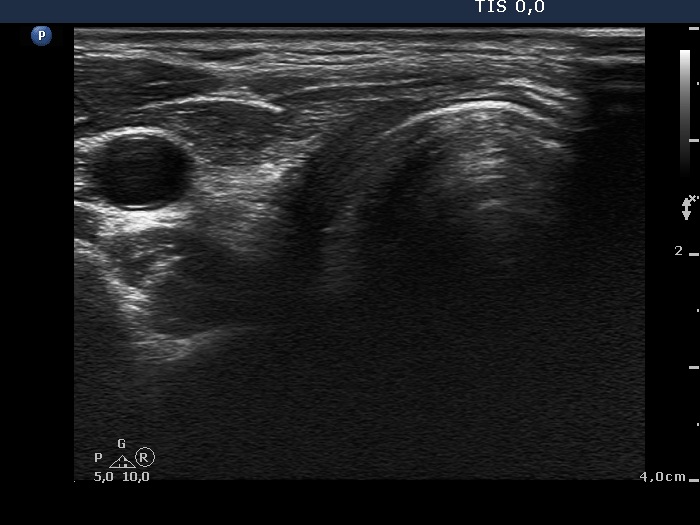

First examination - before surgery (first and second rows of images)

Ultrasonography. The right lobe was echonormal. There was a moderately hypoechogenic, inhomogeneous nodule with blurred borders in the left side of the isthmus. Another cystic nodule was present in the left thyroid.

Cytology of the solid nodule resulted in papillary cancer.